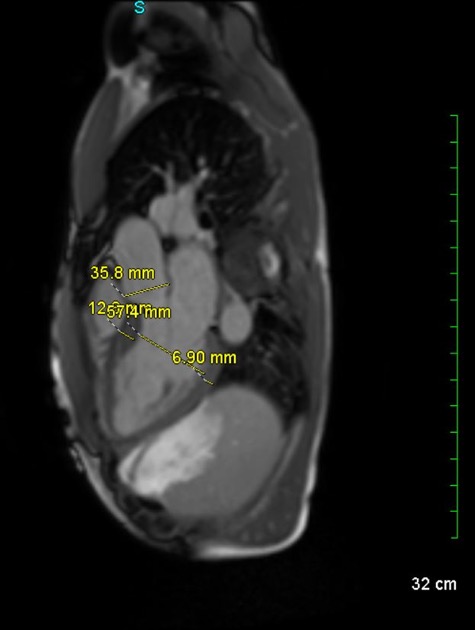

Case Presentation: A 39-year-old man presented with family history of arrhythmogenic right ventricular cardiomyopathy (ARVC). He reported palpitations with exercise. Cascade genetic testing was positive for plakophilin-2 gene mutation. EKG demonstrated sinus bradycardia with possible epsilon wave in V1 and right-axis deviation. Transthoracic echocardiogram was normal. Cardiac MRI (CMR) showed right ventricular free wall thinning and abnormal enhancement suggestive of fatty infiltrates. Genetic testing, EKG, and CMR supported ARVC. Holter revealed intermittent intraventricular conduction abnormality varying from narrow to wide complex with varying PR interval consistent with an intermittent RBBB. Mobile cardiac telemetry uncovered a wide complex rhythm reaching 150 bpm, lacking discernible P-waves, suggesting monomorphic ventricular tachycardia in suspected ARVC or possible supraventricular tachycardia with aberrant conduction. Electrophysiology study revealed atrioventricular node reentrant tachycardia (AVNRT) with an intermittent RBBB. Second opinion disputed previous CMR findings ruling them inconsistent with ARVC. Our patient was diagnosed with AVNRT with aberrant conduction and underwent ablation with no planned cardiac defibrillator for now.